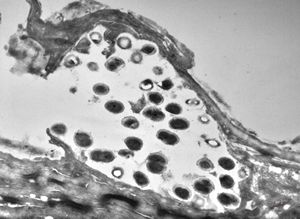

F, 1m. | sepsis - mycotic dermal lesions

M, 57y. | dermal mycotic lesion

M, 57y. | dermal mycotic lesion … toluidine-blue stained semithin section